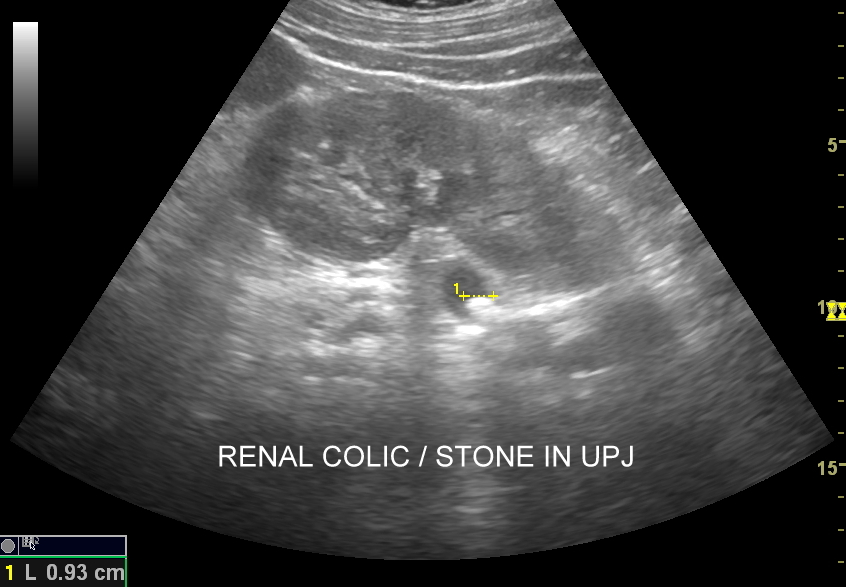

Badania obrazowe służące wykrywaniu kamicy moczowej to badanie RTG, CT, lecz przede wszystkim badanie USG. W badaniu USG nerek w prezentacji B kamica nerkowa widoczna jest w sytuacji, gdy złogi są odpowiednio uwapnione, odpowiednio duże oraz nie zlewają się z zatoką tłuszczową miedniczki nerki. Zasadniczo złogi w trybie B będą widoczne wyraźniej, gdy położone są w miąższu nerki; z kolei w miedniczce nerkowej, gdy są na tyle duże, że dają artefakt cienia. Czasem w celu uwidocznienia złogu przydatne jest wyłączenie wspomagania typu x-beam.

Ważnym trybem pomocniczym jest color-Doppler, w którym to trybie uzyskuje się tzw. artefakt migotania, często nawet na bardzo drobnych złogach niewidocznych w trybie B. Uzyskanie efektu migotania jest niestety zależne o jakości aparatury USG, a także od ustawień Dopplera i software’u.